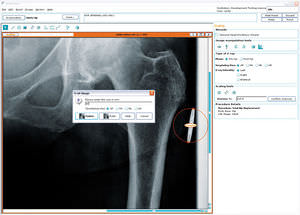

software de planificación preoperatoriaHip Arthroplasty

... OrthoView se desarrolló para ofrecer un completo sistema de planificación prequirúrgica y aplicación de plantillas para el Reemplazo de articulaciones. ¡Un cirujano que use OrthoView 6.0 con SmartHip puede aplicar una plantilla para ...

OrthoView